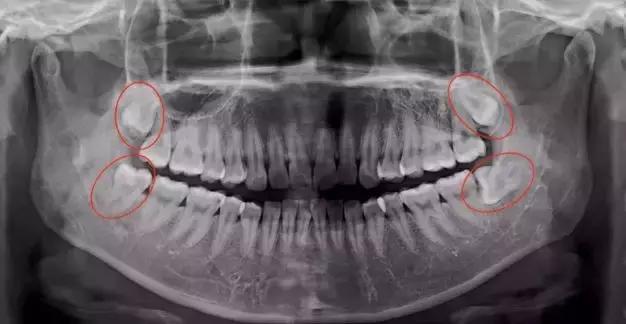

为何采取全麻拔牙而非门诊拔牙,刘伟东医生解释说:鉴于小伟的智齿所在位置不佳,深埋在骨头里,并与下颌神经紧密相连,如果门诊局部麻醉拔牙,风险相对会高,拔牙感受也会痛苦。为减低风险,减少不适,建议小伟采取全麻下拔牙。

▲上图小伟的智齿位置

“该采取全麻住院拔牙还是门诊拔牙,这还要根据患者实际智齿位置而定,我们会结合口腔X片等作为参考给出综合建议。”刘医生说。